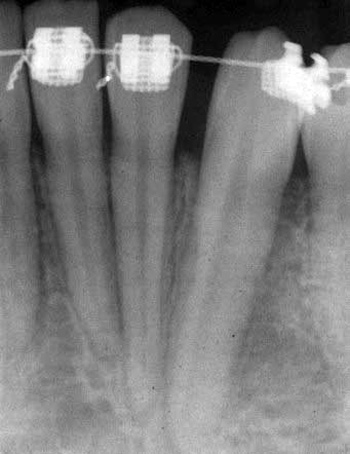

En 12 år gammel pike ble henvist for behandling av en cyste ved tann 33. Tannen var tidligere blitt frilagt flere ganger, og tann 73 var fjernet. Da var det ingen normal apikal resorpsjon av roten på 73. Røntgenologisk var der en 7x7 mm radiolucens distalt ved roten fra emalje-sement-grensen og til midten på roten (figur 3). Den tentative diagnose var lateral periodontal cyste. Ved operasjonen ble løsmasket bløtvev fjernet fra buccalsiden og sendt til histologisk undersøkelse. Diagnosen var AOT.

Figur 3. Kasus 1: Adenomatoid odontogen tumor distalt for tann 33.